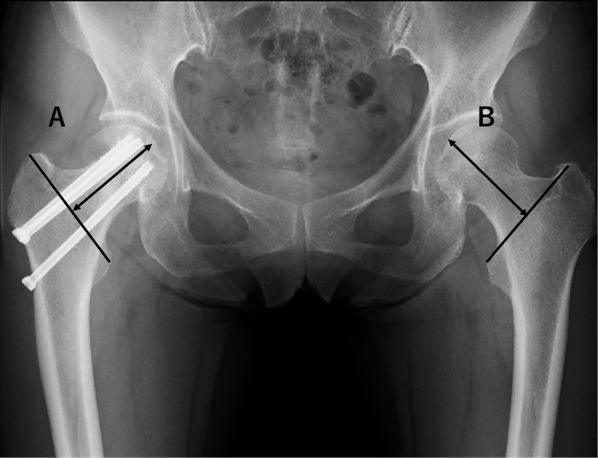

The objective of this study was to evaluate and compare the clinical and radiographic outcomes between in situ fixation and fixation after reduction of severe valgus-impacted femoral neck fractures in patients aged 65 years or older. This was a multicenter retrospective study of 561 patients who underwent open reduction and internal fixation for femoral neck fracture. From this population, we selected patients aged 65 years and older with severe valgus-impacted femoral neck fractures characterized by a Garden alignment index greater than 15 degrees compared to that on the non-injury side. After exclusion criteria were applied, the study included 92 patients who were categorized into two groups: in situ fixation group (n = 56) and fixation after reduction group (n = 36). Our analysis covered patient demographics, surgical details, postoperative complications, radiographic evaluations, Numeric Rating Scale for pain, and Parker's Mobility Score for clinical outcomes. Bone union was achieved in all patients. The incidence of avascular necrosis was consistent between the groups. Patients in the reduction group reported lower Numeric Rating Scale scores (mean: 0 vs 2, p = 0.003) and higher Parker's Mobility Score scores (mean: 7 vs 6, p = 0.009) compared with the in situ group. Radiographically, the reduction group showed significantly lower femoral neck shortening (mean: 4.75 mm vs 5.75 mm, p = 0.049) and a reduced length of cannulated cancellous screw backout (mean: 3.4 mm vs 5.4 mm, p = 0.007) at the final follow-up. Fixation after reduction for severe valgus-impacted femoral neck fractures in patients aged 65 and above appears to be a safe and effective approach.